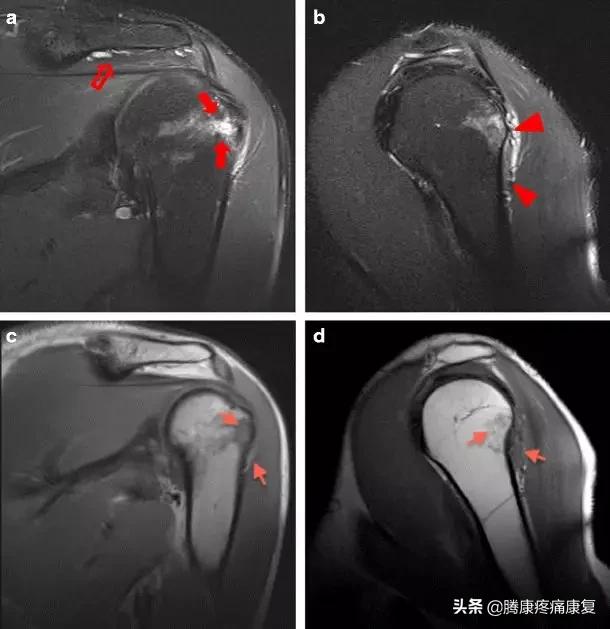

由于疫苗大多数与用来刺激机体产生抗体,所以SIRVA刺激机体的免疫反应导致慢性滑囊炎、粘连性关节囊炎、肩袖肌腱病、骨髓水肿、骨坏死等并发症。

当疫苗被错误的注射后,由于疫苗注射或针头创伤错误的进入肩关节滑囊或其周边区域,引起免疫反应导致炎症,引发一系列典型的症状包括: